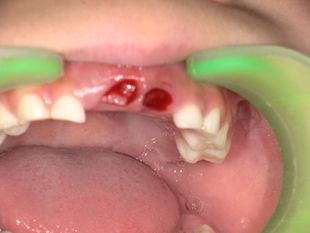

永久歯の舌側転位 乳歯の抜歯前 Before

乳歯の抜歯後 After

診察の結果、上の前歯の永久歯がすでに萌出しているにもかかわらず、乳歯が残っている状態でした。

これは乳歯晩期残存と呼ばれる状態です。

以上の理由から、残存している上の前歯2本の乳歯を抜歯する必要があると診断しました。

治療では、痛みを最小限に抑えるため局所麻酔を行い、上の前歯の乳歯を慎重に抜歯しました。

抜歯後は出血がしっかり止まっていることを確認し、治療を終了しています。